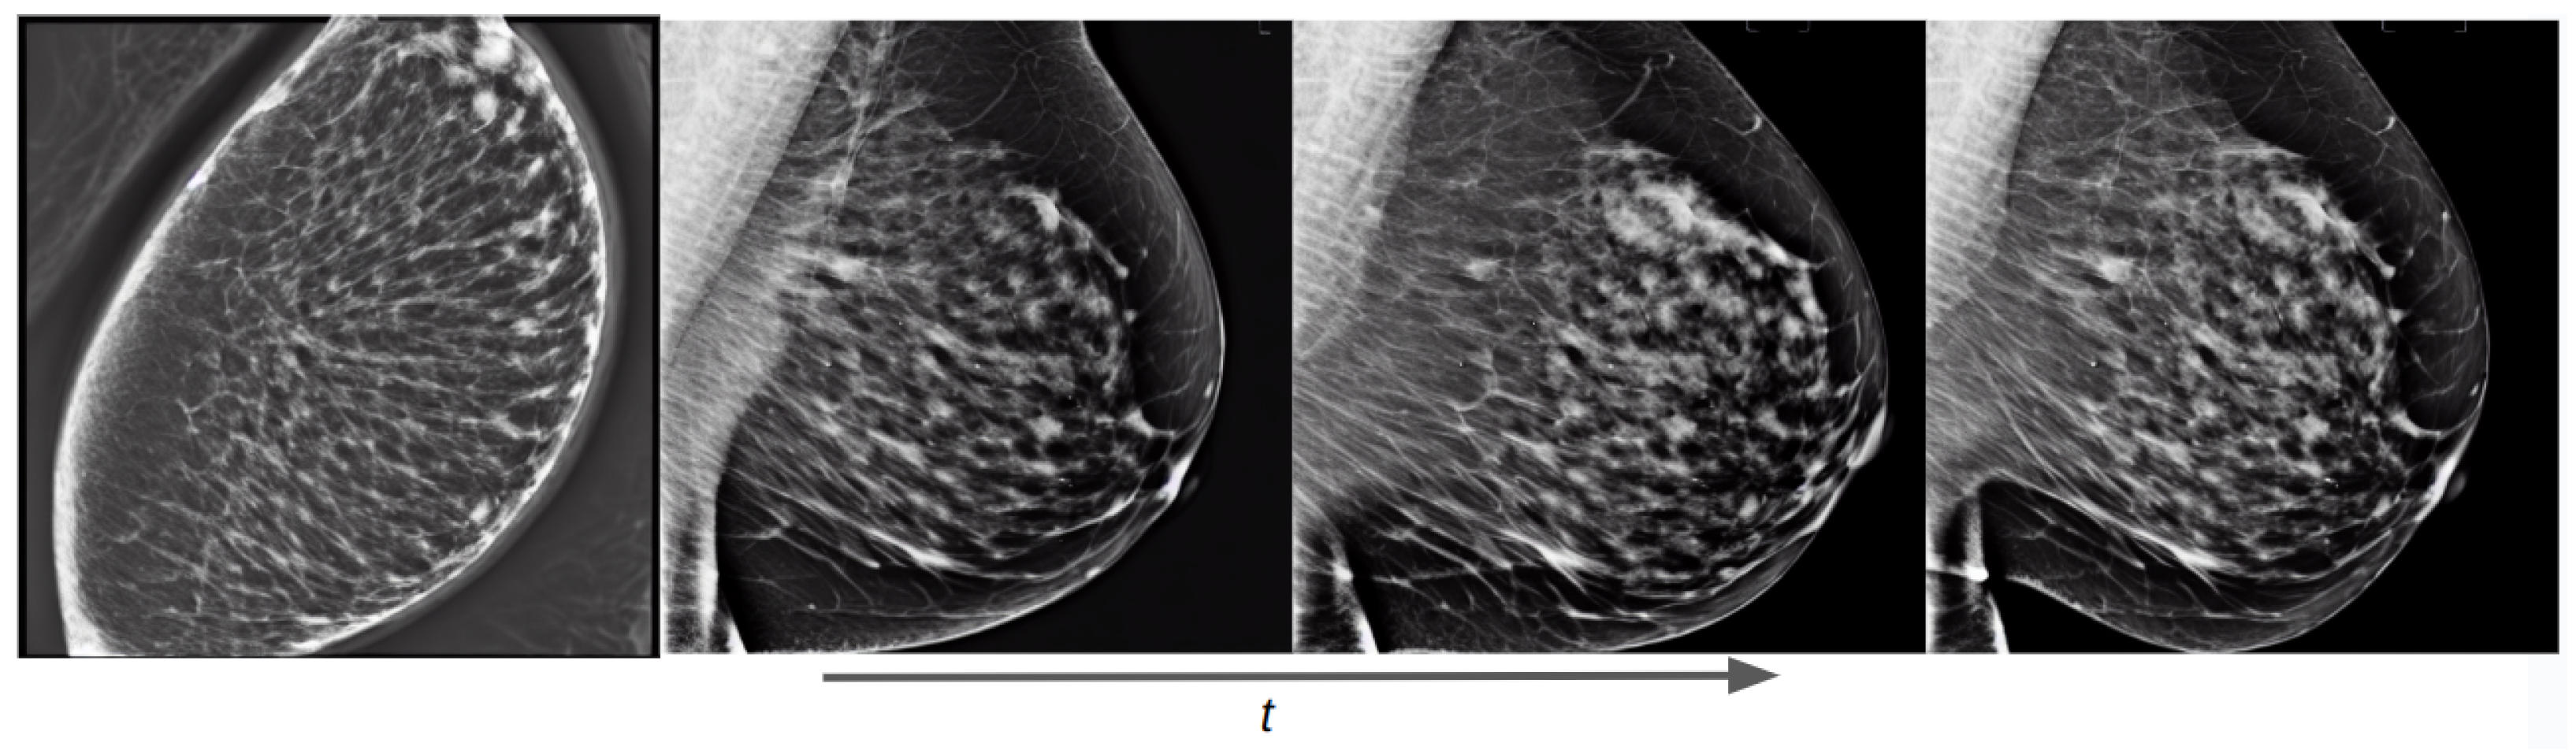

3.2. Lesion Generation